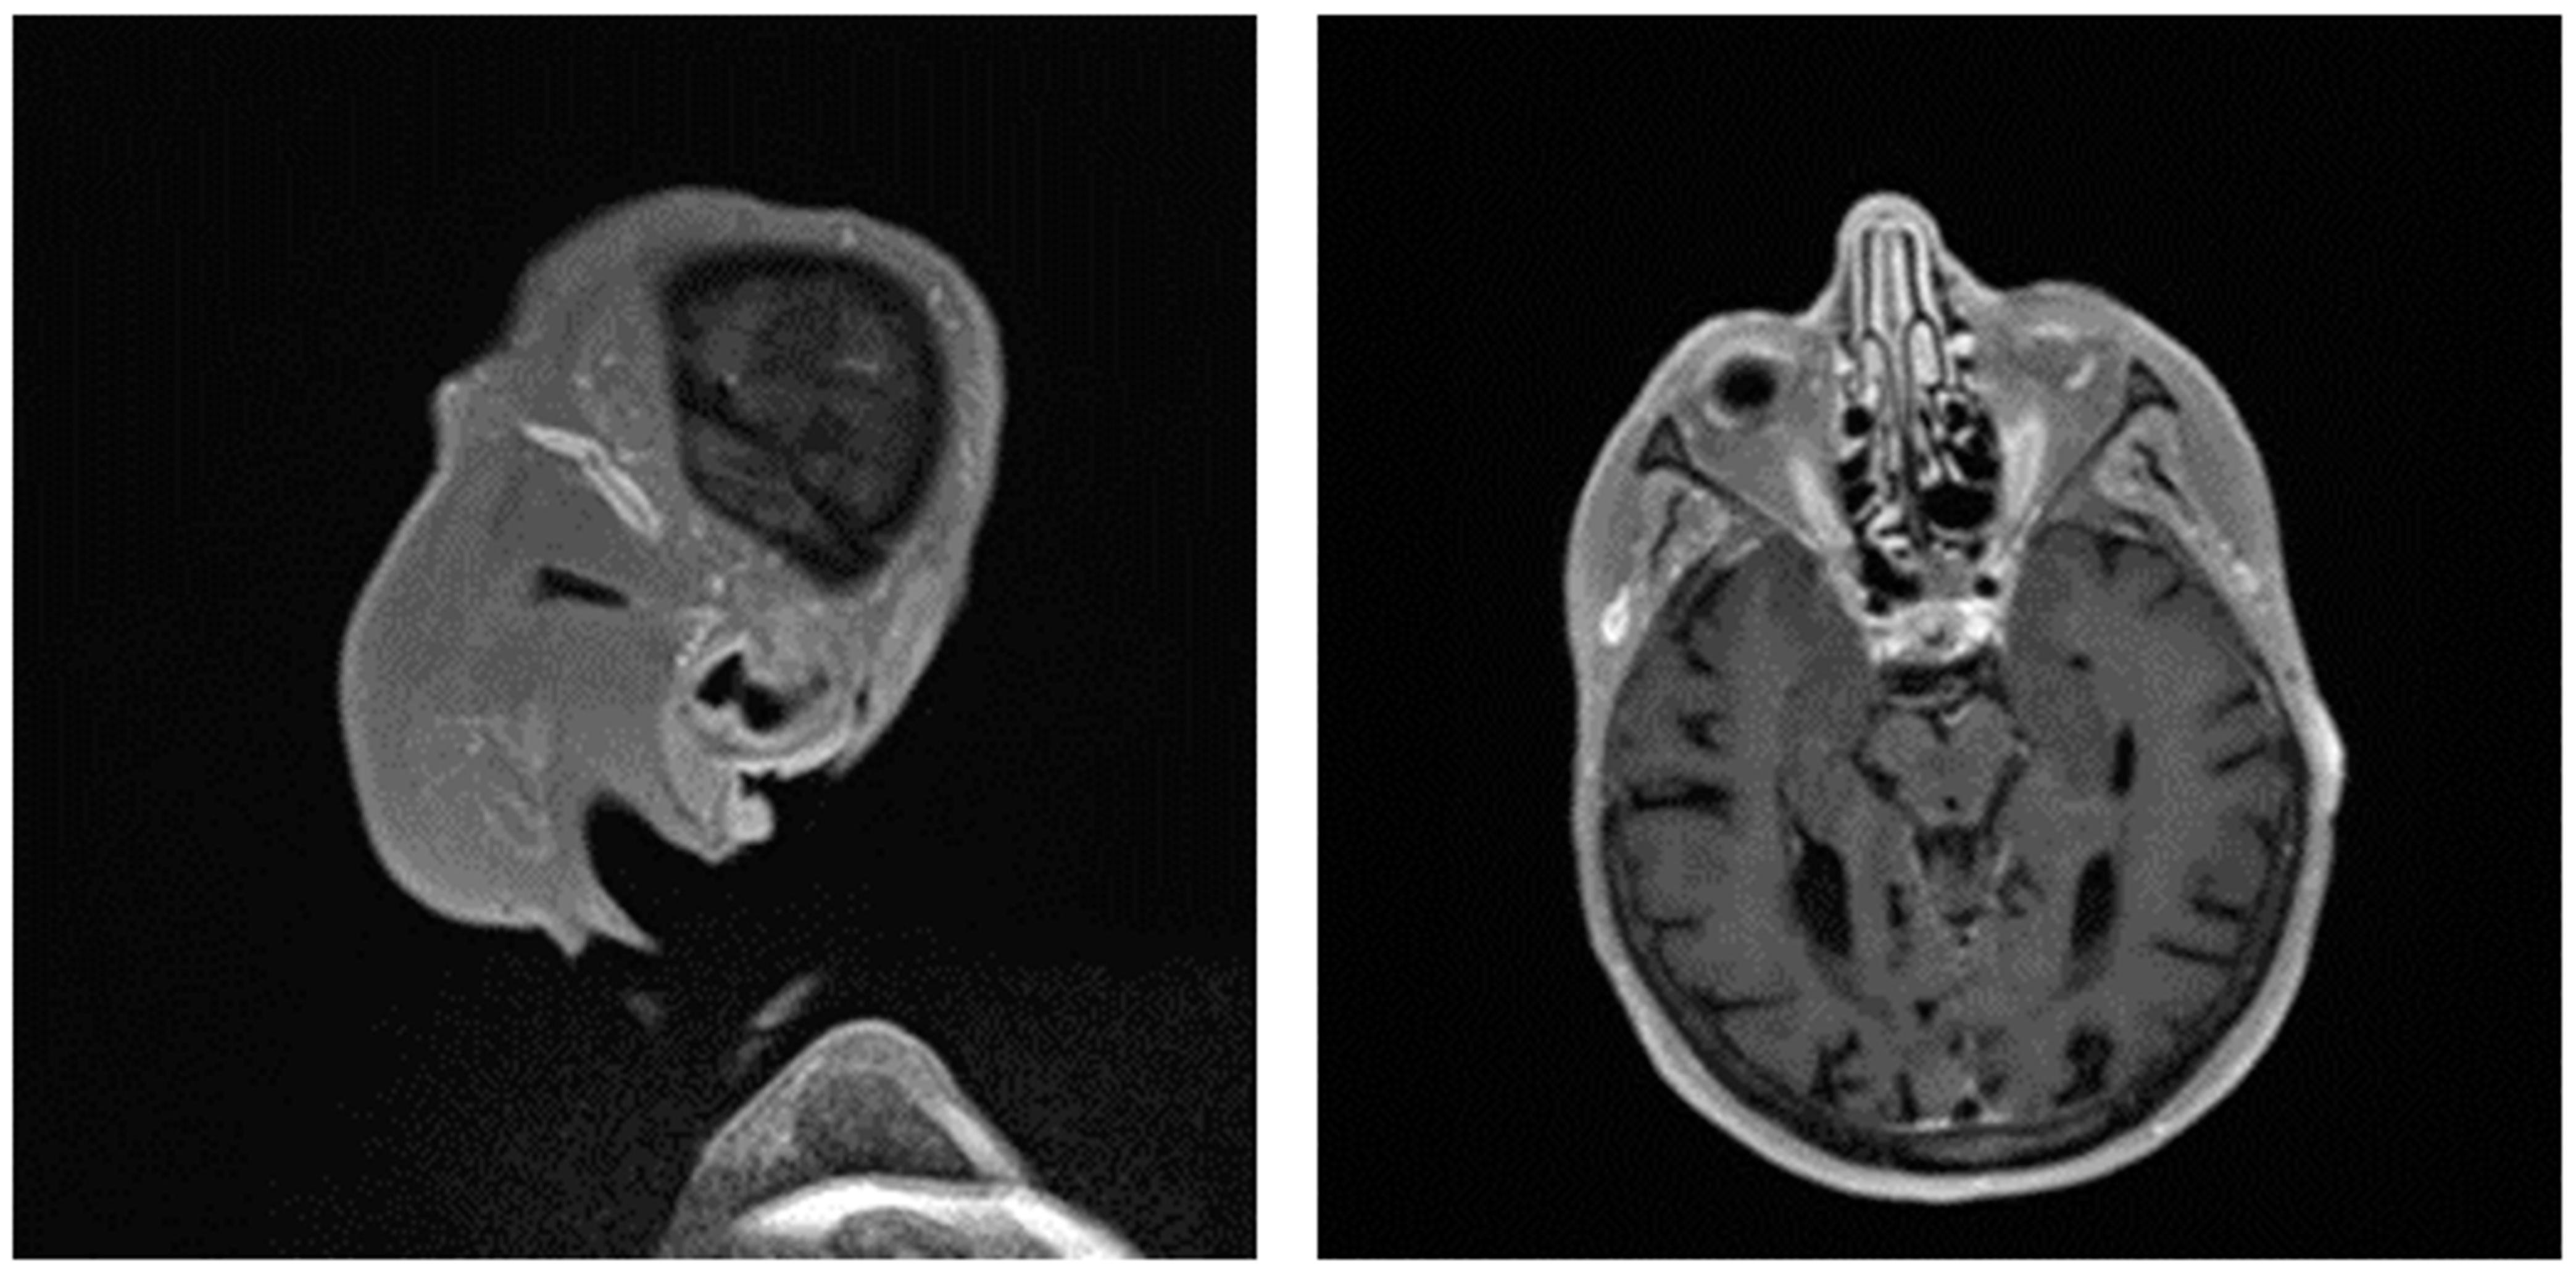

Figure 2. Ultrasonographic findings in patients with large vessel vasculitis: (A,B): B-mode US with the finding of concentric carotid intima-media thickening in a patient with Takayasu’s arteritis ((A) longitudinal plane, (B) transversal plane). (C). B-mode US: carotid intima-media thickening in a patient with giant cell arteritis. (D): Power Doppler US in a patient with temporal arteritis (typical “HALO” sign). Courtesy of Dr. Konstantinos Triantafyllias, Rheumatology Center, Rhineland-Palatinate.

Giant cell arteritis (GCA) affects typically large- and medium-sized arteries, including the carotid arteries and their extracranial branches, as well as the aorta and its branches [48]. Symptoms of GCA include headache, jaw claudication, tenderness of the temporal artery, and low-grade fever [49]. Typical complications of GCA include acute loss of vision and aortic aneurysms, which in turn can lead to more severe complications like stroke or aortic dissection [49,50]. GCA is frequently linked with polymyalgia rheumatica (PMR), characterized by muscle pain and bilateral morning stiffness in the proximal extremities. At a microscopic level, giant cells infiltrate the vascular wall, leading to an occlusion of the affected blood vessels and thus to ischemia of the tissue to be supplied [51]. The diagnosis of PMR/GCA is usually based on clinical presentation, imaging, temporal artery biopsy (Figure 2C,D, Figure 3 and Figure 4), and the ACR/EULAR classification criteria [49,52].